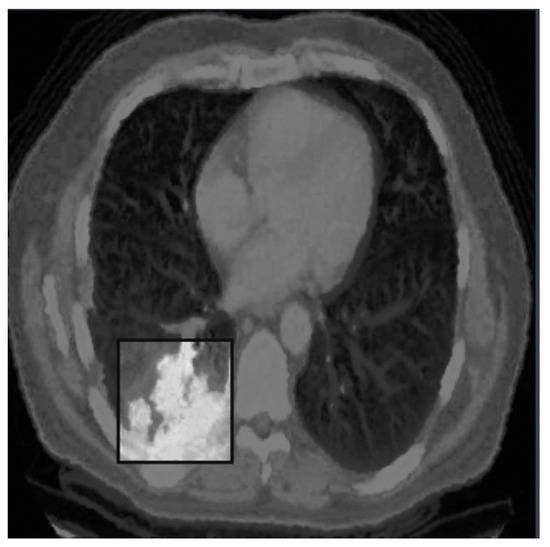

- Adenocarcinoma (Blue Line):

- -

- The blue line represents the precision–recall relationship for the adenocarcinoma class.

- With an average precision (AP) of 0.734, the model performs relatively well in detecting adenocarcinoma, maintaining high precision and recall values.

- Cancer (Orange Line):

- The orange line represents the performance for the cancer class.

- An AP of 0.588 indicates moderate performance, with a noticeable drop in precision as recall increases, suggesting that the model struggles more with this class compared to adenocarcinoma and nodules.